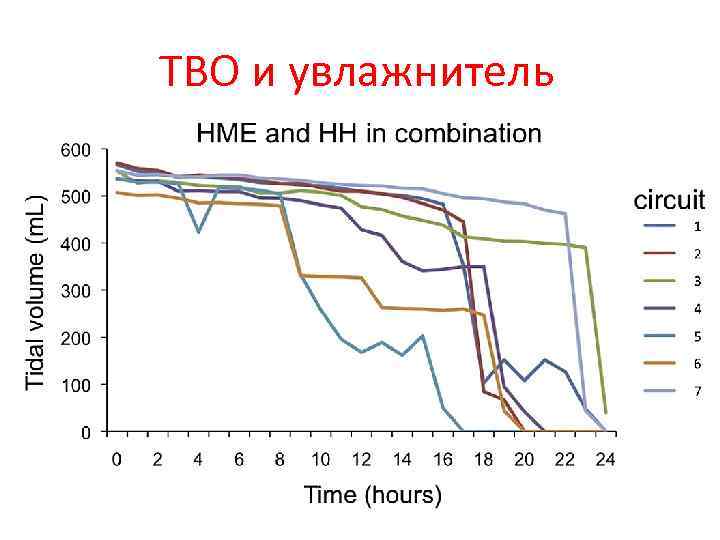

ТВО и увлажнитель

ТВО и увлажнитель